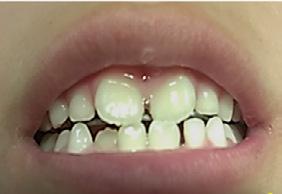

Caso 1

Paciente de 4 años y 8 meses, femenino que se presentó acompañada de su madre para valoración y consulta, presentando dentición mixta y movilidad clase 3 en el diente 71 y caries en diente 72, normoclusión molar y mordida cruzada anterior (Figura 1). Se realizó el plan de tratamiento integral, señalando la necesidad de llevar a cabo la exodoncia y la restauración. Dada la característica clínica presentada, se le conminó a la madre a atender ortodóncicamente a

Figura 1. Figura I. Exodoncia del 71 y caries proximal en diente 72.